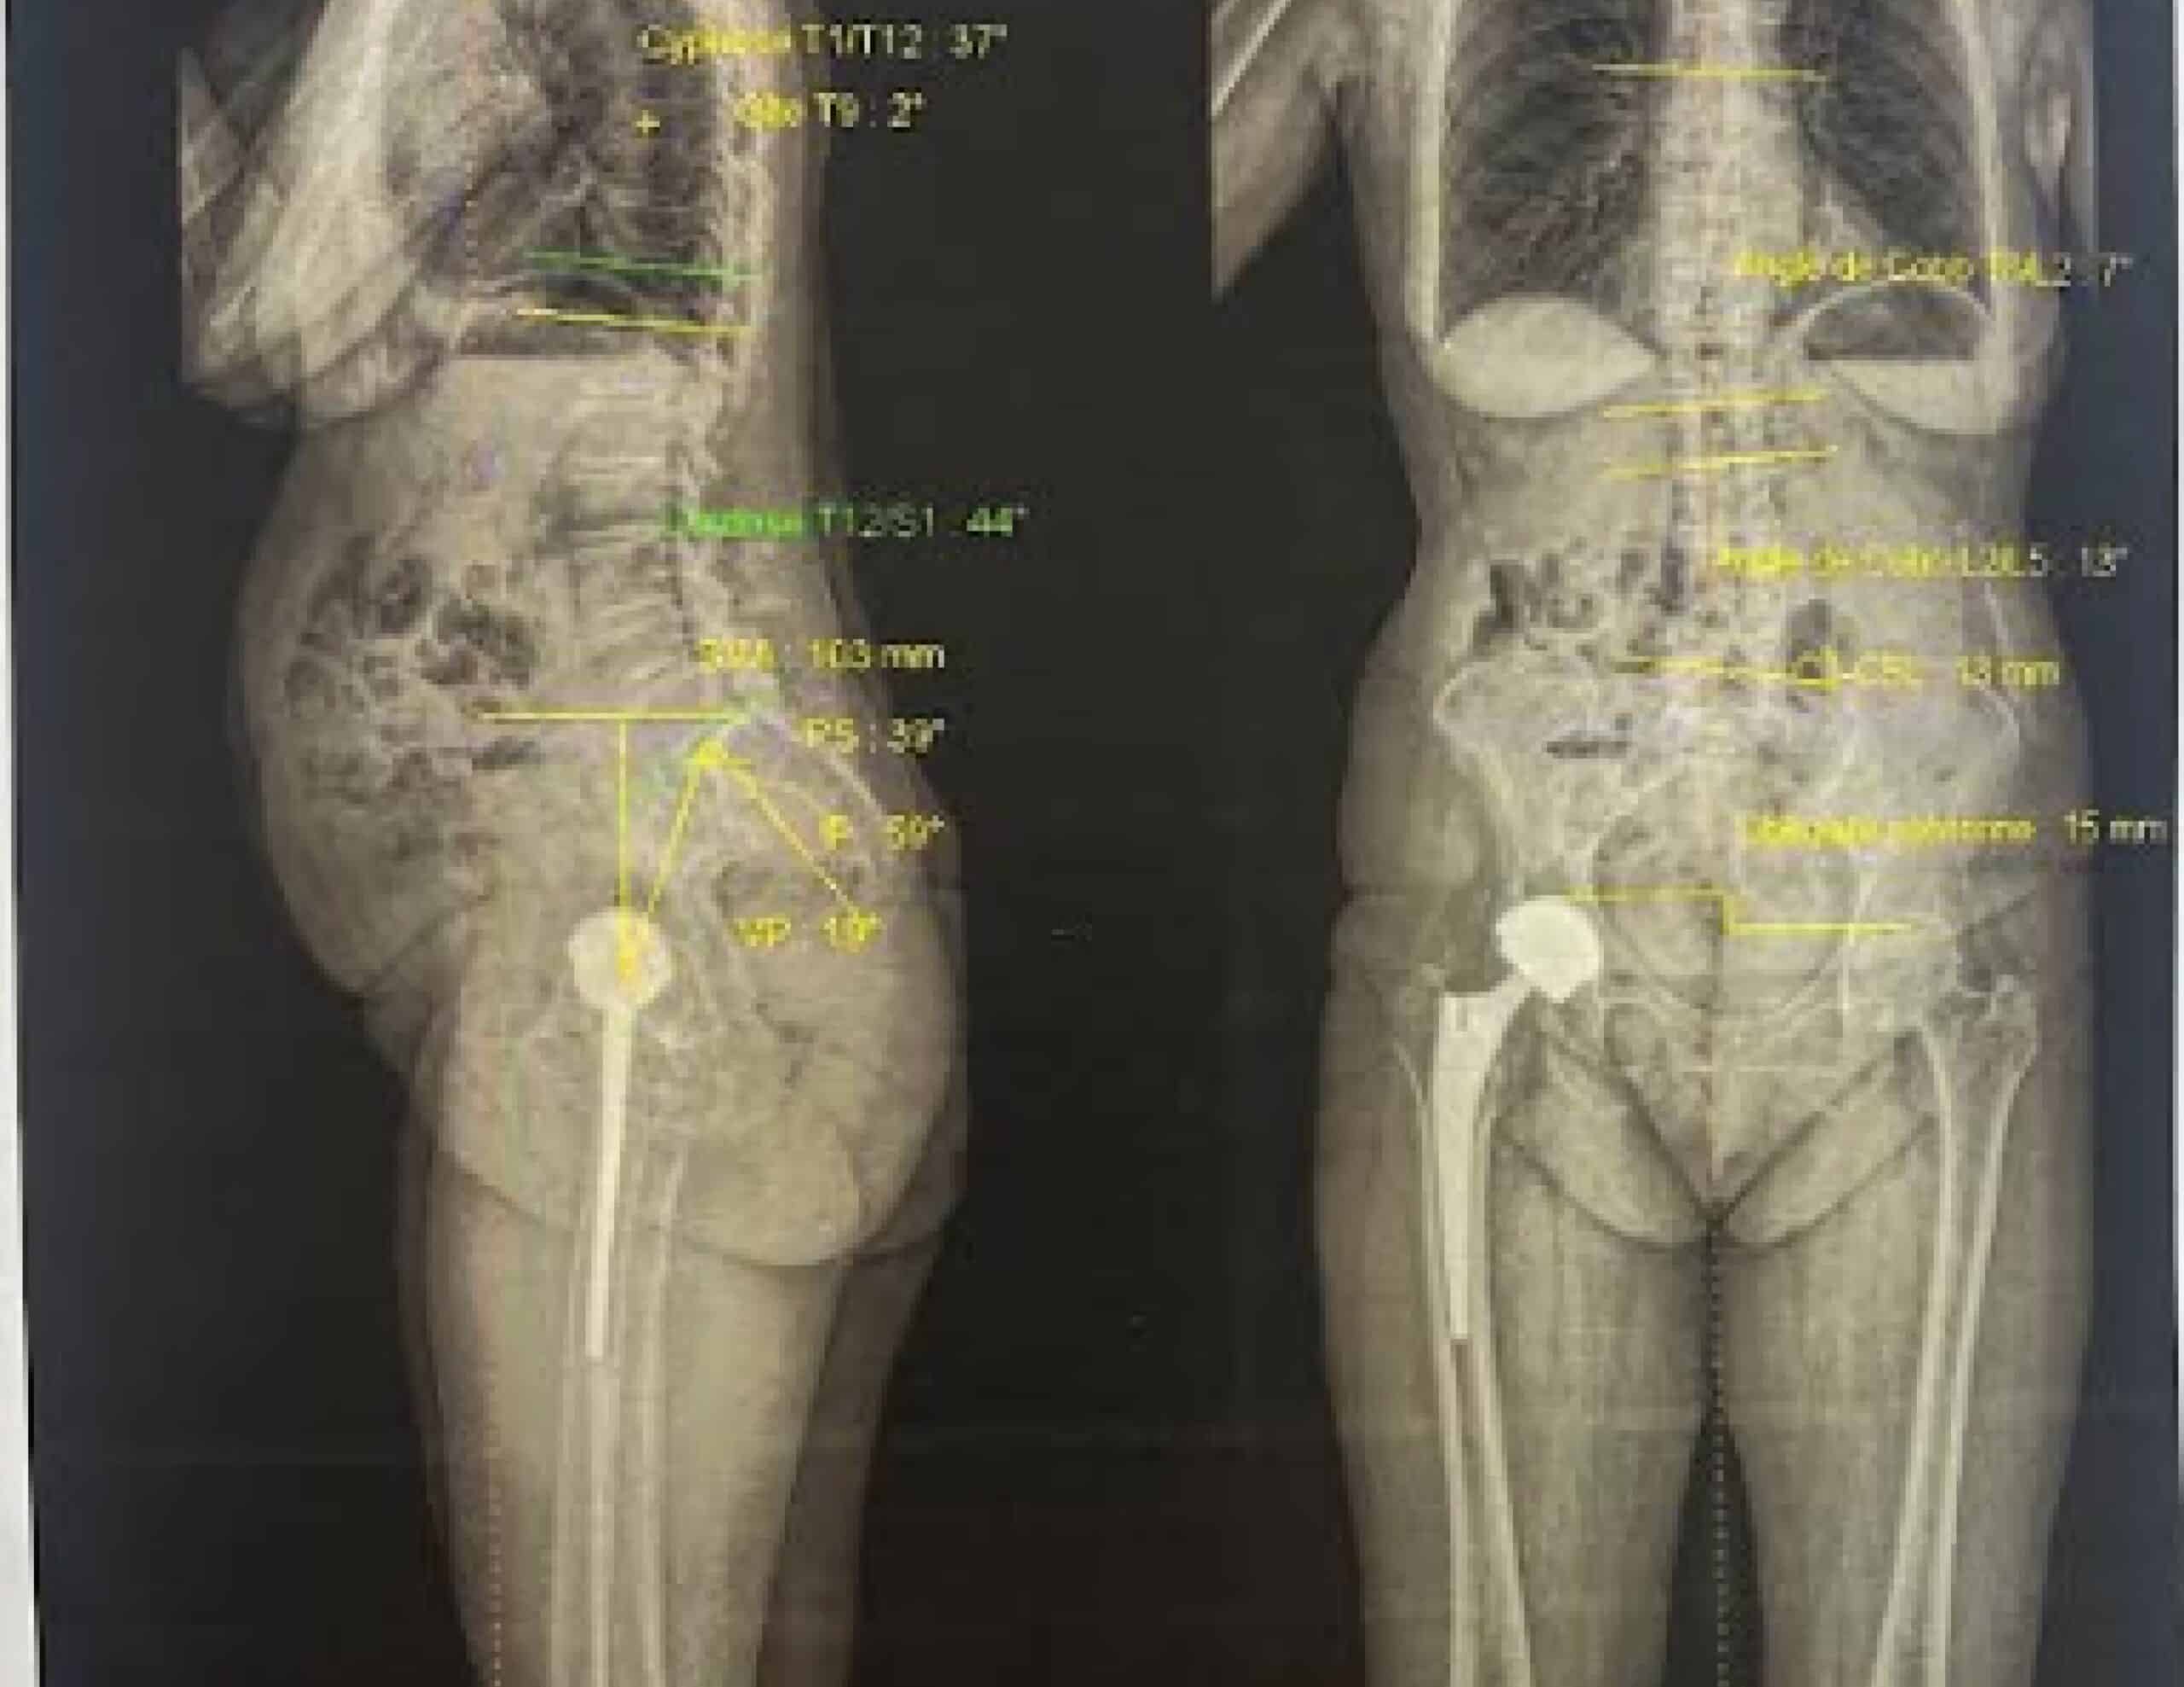

EOS imaging is a low-radiation radiological technique that allows full-body assessment in a standing position. It provides an overall view of the spine and lower limbs and makes it possible to visualize and quantify deviations in the frontal, sagittal, and axial planes.

Advantages of EOS Imaging

- Useful in cases of scoliosis or pelvic obliquity

- Allows assessment of lumbopelvic-femoral parameters (relationships between the lumbar spine, sacrum, pelvis, and femur)

- Reveals lower-limb deformities : genu valgum, genu varum, knee or hip flexion contractures

- Measures bone segment lengths and detects leg length discrepancies

Limitations of EOS Imaging

EOS does not provide detailed information about bone structure. It is a global skeleton model, not suitable for millimetric bone analysis and does not allow the design of custom-made implants.

When should EOS imaging be added?

EOS may be prescribed in addition whenever spinal disorders or global lower-limb deformities are present.

Thus CT scan remains the key examination for precise 3D planning, while EOS provides a full-body weightbearing assessment.